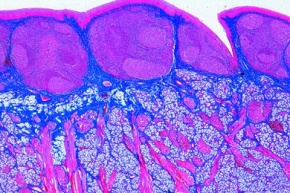

Mikropräparat - Weicher Gaumen, quer

12,14 €

inkl. 19 % USt zzgl. Versandkosten

Mikropräparat - Weicher Gaumen, quer

Zum Artikel